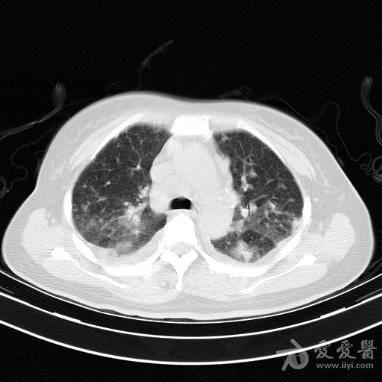

三第三题:如下图所示,病变表现为双肺多发斑片,磨玻璃影.

左下肺斑片状高密度影,边缘模糊,并可见小囊腔,内有气-液平面.

肺内多发斑片影?